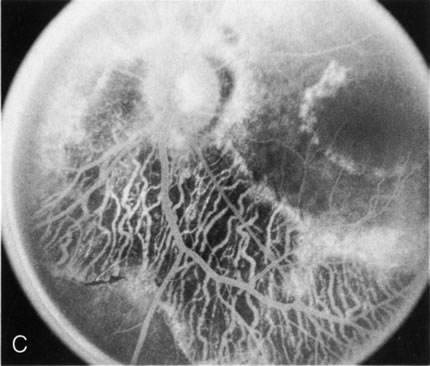

Fig. 4. Choroideremia and choroideremia carrier. A. The choroidal atrophy in this affected male is not apparent in the fundus. B. However, the angiogram shows diffuse atrophy of the choriocapillaris with persistent visualization of the larger choroidal vessels. C. This carrier female has peripapillary choroidal atrophy and diffuse pigment mottling. D. The patchy areas of focal choroidal atrophy that occasionally occurs in carriers is evident on angiography.

The typical carrier female, with focal or diffuse pigment mottling, does not show choroidal atrophy. However, a few carrier females have a more severe form with focal areas of choroidal atrophy. The presence of these areas, and possible progression, can be documented by FA (Fig. 4C and D). These carriers exhibit a mosaicism, which is explained by the Lyon hypothesis of random X-chromosome inactivation.